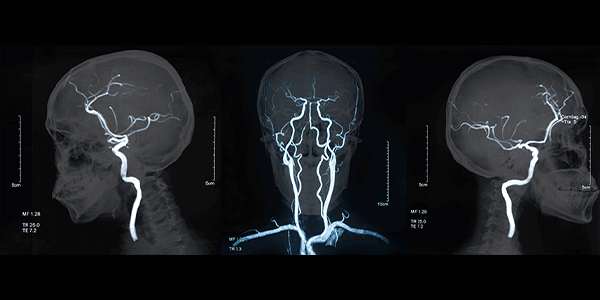

Beyin anjiyografi, beyin damarlarındaki olası tıkanıklık, daralma, anevrizma (baloncuk), ve diğer vasküler sorunları tespit etmek için kullanılan özel bir görüntüleme yöntemidir. Bu test, beyin damarlarının detaylı bir haritasını sunar ve damar hastalıklarının tanısında oldukça önemlidir.

Beyin Anjiyografi Neden Yapılır?

Beyin anjiyografi aşağıdaki durumlar nedeniyle yapılır:

• İnme veya geçici iskemik atak (TIA) belirtilerini araştırmak

• Beyin anevrizması şüphesi

• Beyin damarlarında tıkanıklık veya daralma

• Beyin tümörü veya vasküler malformasyonların değerlendirilmesi

• Kafa travması sonrası damar hasarını incelemek